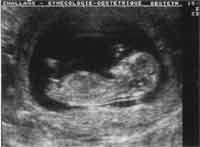

Abdominale